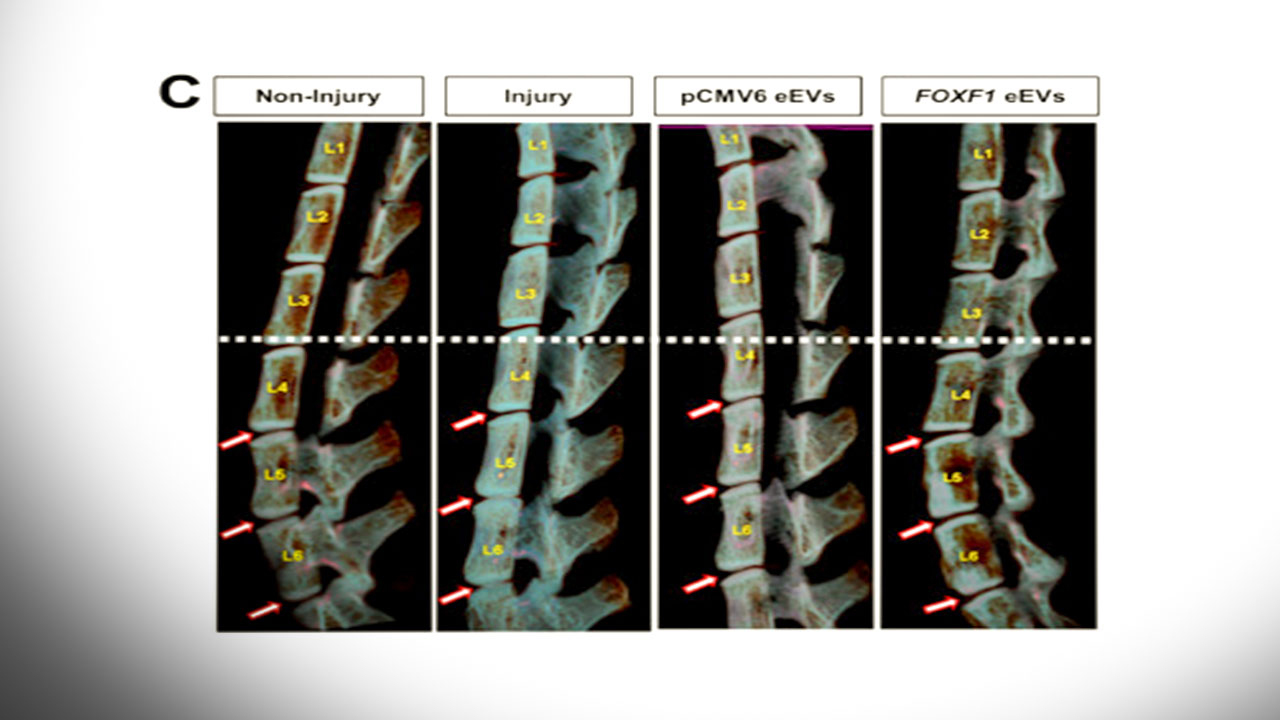

با ارزیابی نتایج بیش از ۱۲ هفته، محققان از طریق تصویربرداری، تجزیه و تحلیل بافت و تستهای مکانیکی و رفتاری دریافتند که این روش ژندرمانی توانسته است تا یکپارچگی ساختاری و عملکرد را به دیسکهای انحطاطی بازگرداند و همچنین موجب کاهش علائم کمردرد در موشها میشود.

در آزمایشها، موشهایی با دیسک کمر آسیبدیده تحت درمان با نانوذرات FOXF1 قرار گرفته و نتایج با موشهای کنترل مقایسه شد. در مقایسه با گروه شاهد، دیسکها در موشهای دریافتکننده ژندرمانی، بهبود قابل توجهی را تجربه کرد. آزمایشهای رفتاری نشان داد که درمان باعث کاهش علائم درد در موشها میشود.